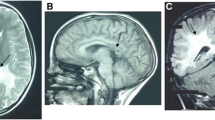

We diagnosed an adrenomyeloneuropathy (AMN) patient with a double novel missense mutation, c.284C>A (p.A95D) and c.290A>T (p.H97L) in a single ABCD1 allele. In skin fibroblasts from the patient, no ABCD1 protein was detected by immunoblot analysis, and the C24:0 β-oxidation activity was decreased to a level at which the ABCD1 protein was absent. To determine the responsible gene mutation in the patient, we constructed three kinds of mutated ABCD1 gene expression vectors (c.284C>A, c.290A>T or c.284C>A/c.290A>T) and transfected them into CHO cells stably expressing GFP-SKL (CHO/GFP-SKL cells) or CADDS fibroblasts lacking the ABCD1 gene. ABCD1 (p.H97L) displayed the correct peroxisomal localization in CHO/GFP-SKL cells, but ABCD1 (p.A95D) and ABCD1 (p.A95D/p.H97L) were diffuse in the cytosol. Furthermore, ABCD1 (p.H97L) was detected by immunoblot analysis and restored the C24:0 β-oxidation activity in the CADDS fibroblasts, as the wild type ABCD1 did. On the other hand, ABCD1 (p.A95D) and ABCD1 (p.A95D/p.H97L) were not detected and the C24:0 β-oxidation activity was not restored. These results clearly show that c.284C>A is the responsible gene mutation, whereas c.290A>T is a novel polymorphism.